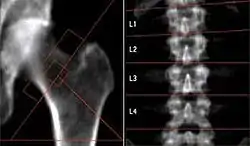

In addition to working through the risks, there will be separate investigations of NASA databases. For example, "How Long Does It Take to Rebuild Bone Lost During Space Flight?" from url=http://www.nasa.gov/mission_pages/station/research/subregional_bone.html.

The image on the right shows the loss of bone mass apparently due to long-term microgravity on the International Space Station. "[A]stronauts, on average, lost roughly 11 percent of their total hip bone mass over the course of their mission." from this report.

"The success of human exploration missions depends on finding countermeasures to overcome such effects on crew members. There are important synergies between osteoporosis research on Earth, and studies of bone loss and recovery in healthy astronauts in space. Each area of study complements the other." by Julie Robinson, International Space Station program scientist at NASA's Johnson Space Center in Houston, from the same report.